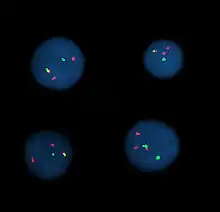

La cytogénétique est l'étude des phénomènes génétiques au niveau de la cellule, c’est-à-dire au niveau des chromosomes sans la nécessité d'extraire l'ADN : anomalies chromosomiques (de nombre et de structure), recombinaison de chromosomes, etc. Les techniques utilisées sont principalement la réalisation de caryotype, les méthodes de FISH (Fluorescent In-Situ Hybridation : hybridation in-situ par des sondes fluorescentes), l'utilisation de puce à ADN.

Hybridation in situ en fluorescence

La technique dite de FISH (Fluorescent In Situ Hybridization) est une technique qui permet de révéler par fluorescence grâce à des sondes d'ADN des séquences sur les chromosomes. Cela permet d'identifier des anomalies chromosomiques lors d'analyses pré- et post-natales. Chaque analyse ne permet d'identifier qu'une seule anomalie, et c'est une technique ciblée, les sondes utilisées ne sont pas choisies au hasard, mais font suite à de précédentes analyses (de biochimie en général).